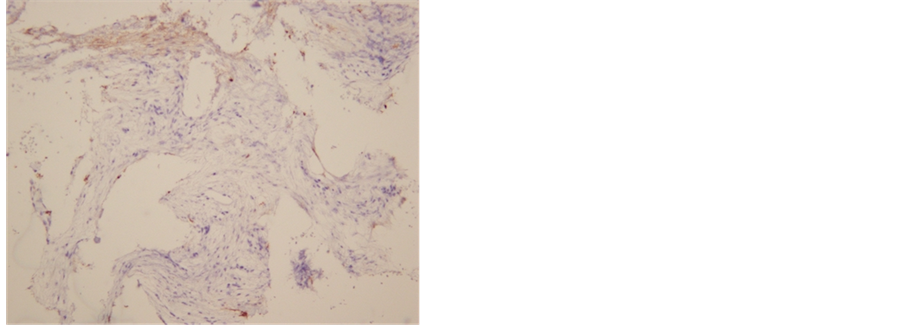

The etiology of the massive osteolysis that occurs in GS syndrome is not well known. This disease occurs most commonly in adolescence and in the second and third decades, although the age range of those affected is between 1.5 and 72 years [7] [8] . There is no incidence of sexual or racial predominance. GS syndrome is diagnosed based on clinical examination, radiological imaging, and biopsy. In this case, the patient was accurately diagnosed using the extracted bone (Figure 4). There are some treatments for GS syndrome, such as radiation therapy [9] , anti-osteoclastic medication, and alpha-2b interferon [10] . Surgical treatment options include resection of the lesion, instrumentation using bone grafts, and prostheses. In this case, the patient has received sirolimus therapy which is used for the treatment of lymphangioleiomyomatosis.

Figure 4. Histopathological image of Mandibular bone (Immunostaining). Accumulation of vasculature which is D2-40 positive can be seen.